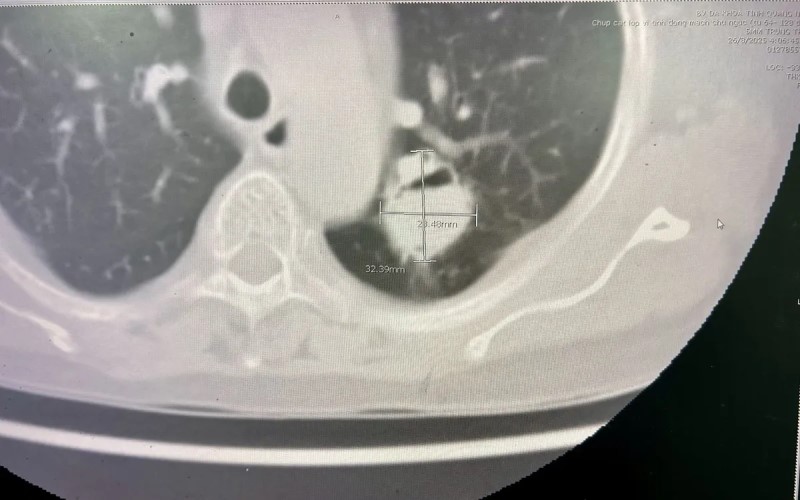

Bệnh nhân Đ.T.L., trú tại Hưng Yên, có tiền sử bệnh phổi tắc nghẽn mạn tính, nhập viện trong tình trạng ho nhiều và ho ra máu tái diễn. Kết quả thăm khám, hội chẩn xác định bệnh nhân có u nấm phổi thùy trên phổi trái, nguy cơ chảy máu nặng nên được chỉ định phẫu thuật cắt thùy phổi.

Trong ca mổ, khối u kích thước hơn 3cm nằm sát rốn phổi, dính nhiều vào thùy dưới, thành ngực và động mạch chủ, khiến việc bóc tách trở nên phức tạp. Sau hơn 2 giờ, ekip phẫu thuật đã cắt trọn thùy phổi chứa u nấm, bảo tồn phần phổi còn lại, đảm bảo thông khí tốt.